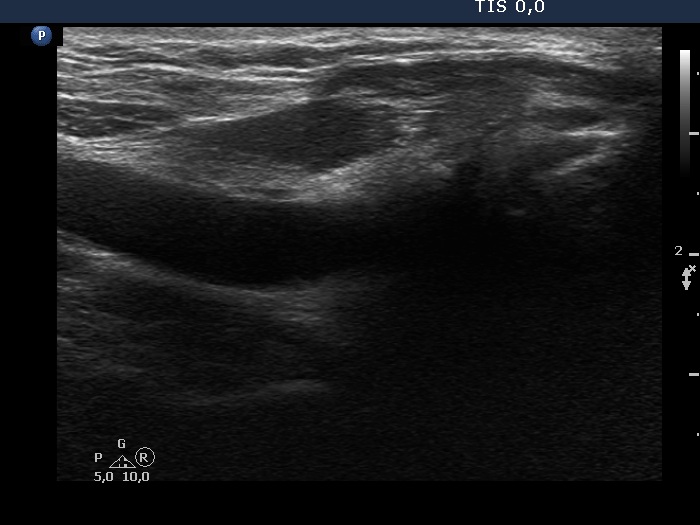

Eleven years after surgery (second and third rows of images):

Ultrasonography. The right lobe remained unchanged. Compared with the previous finding, a much smaller, inhomogeneous mass was found according to the left lobe. A few centimeters above and ventral to the left lobe, a cystic lesion was found within the strap muscle and close to this, an amorphous hyperechoic fragment was also present (see video).